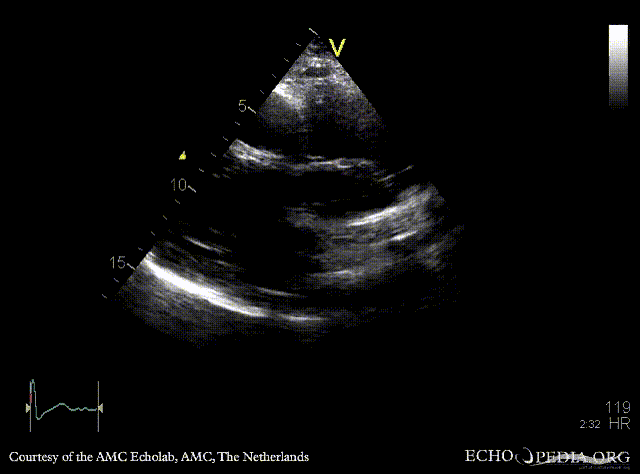

Compression of right atrium

A4CH: Compression of right atrium by aneurysm of ascending aorta PLAX: large aneurysm of ascending aorta, Bentall in situ